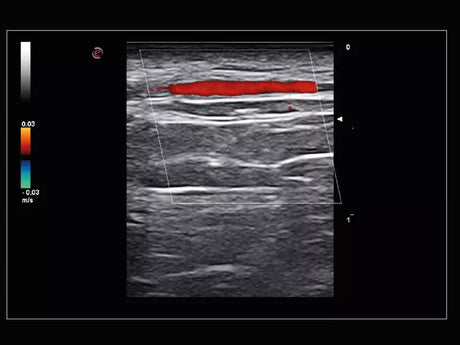

La qualité d’image est au cœur de la philosophie Esaote. Grâce à ses sondes de dernière génération et à son traitement du signal avancé, la marque permet une visualisation fine des structures anatomiques, même les plus profondes. Leurs échographes intègrent des écrans tactiles haute résolution, une interface claire et une connectivité complète, favorisant un flux de travail rapide et efficace.

Les échographes Esaote offrent une restitution d’image d’une grande précision, permettant un diagnostic fiable dans toutes les spécialités. Le traitement numérique optimise le contraste et la netteté, réduisant les artefacts et améliorant la détection des tissus pathologiques. Ces performances sont particulièrement appréciées en gynécologie, où la lisibilité des structures pelviennes ou obstétricales est déterminante.